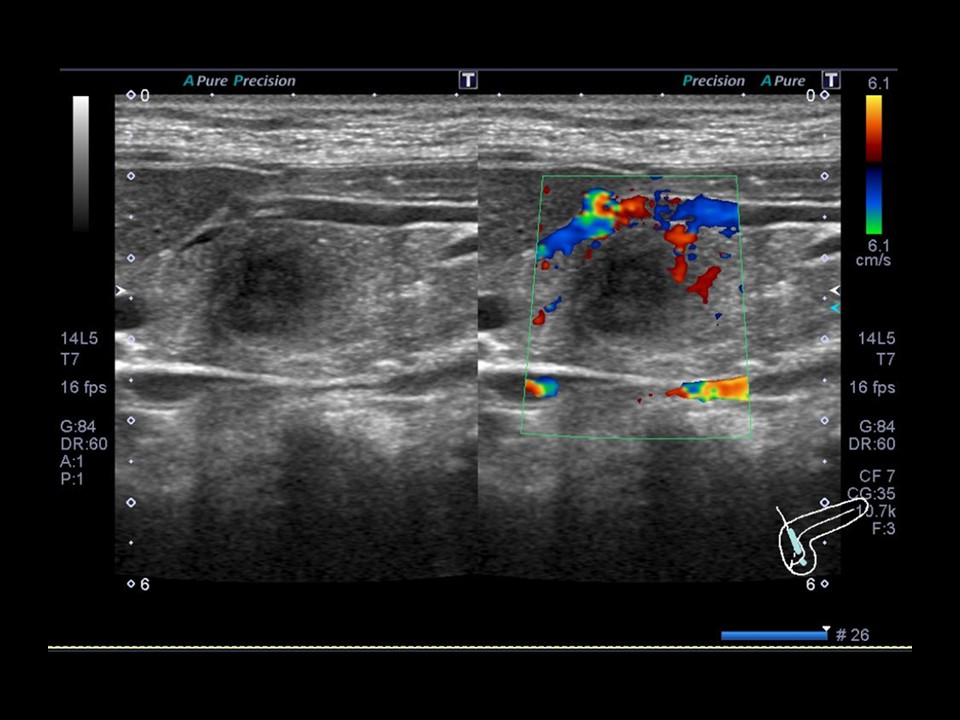

優秀賞

志村 聡子 山王健診センター

診断名:腎癌(腎盂腎癌)

患者:60歳代 男性

使用機種:

Canon Aplio i600

周波数:3.75MHz

コメント(術者の一言)

多数の隔壁を意識し記録しました。特に厚くなっている部分にフォーカスをあてました。無エコー部分と充実部分のコントラストを描出するのに苦慮しました。